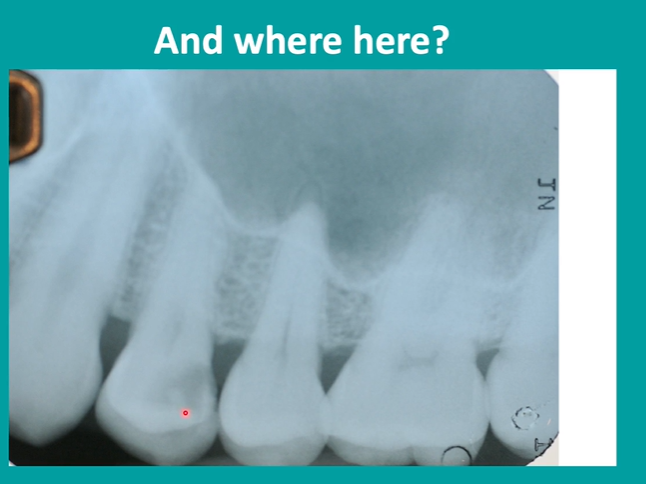

bitewing radiographs in caries detection

electrons need to hit the detector at 90 degrees so we get no crossover of the contact areas

distal of premolar

radiolucency